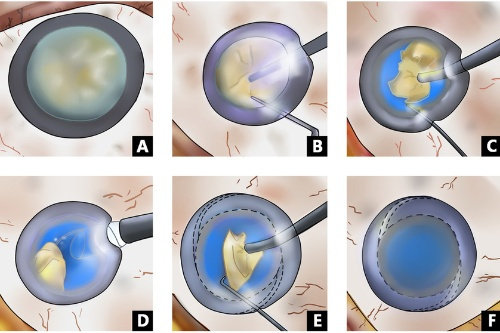

45岁糖尿病患者王先生,因视力骤降就诊,确诊为增殖性糖尿病视网膜病变伴玻璃体出血。

孙医生为其多期实施玻璃体切割手术联合全视网膜光凝,术后6个月视力从0.1修复至0.6。

典型玻璃体手术包含三个关键阶段:

术前准备:超全评估全身状况,定制个性化玻璃体替代方案

精细操作:在显微镜下完成视网膜前膜剥离、激光光凝等步骤

术后管理:采用特殊体位护理,配合***药物治疗